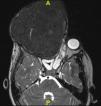

We proceeded to do a contrast enhanced 3-dimensional computed tomography scan of the skull and facial region (Fig. 2A–C). This scan showed a 17cm×12cm×11cm expansile, heterogeneously enhancing soft tissue attenuating mass lesion with multiple hyperdense areas within it; involving the right maxilla, ethmoidal bone and pterygoid plates with cortical bone thinning. No extraosseous soft tissue lesion was noted. Medially the lesion displaced the lateral wall of the right nasal cavity, causing its obliteration. Posteriorly it involved the medial and lateral pterygoid plates; superiorly extending till the inferior orbital rim, causing gross superolateral proptosis and stretching of the right optic nerve. There was no intracranial extension noted, which was confirmed by doing an MRI scan (Fig. 3).

On CT scan, eggshell thinning of the cortical bone by the mass which has a distinct boundary helps it to be radiologically differentiated from fibrous dysplasia, in which the mass blends into the surrounding bone. Ossifying fibroma on T1-weighted MRI shows intermediate signal intensity, which moderately enhances with IV contrast; and on T2-weighted MRI shows hypointense signal.11